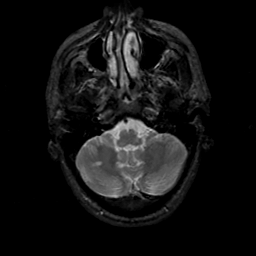

MR Study #19, August 25, 1991 -- Slice #9

[Home][Help][Clinical][Tour 1][Tour 2] Slice 9